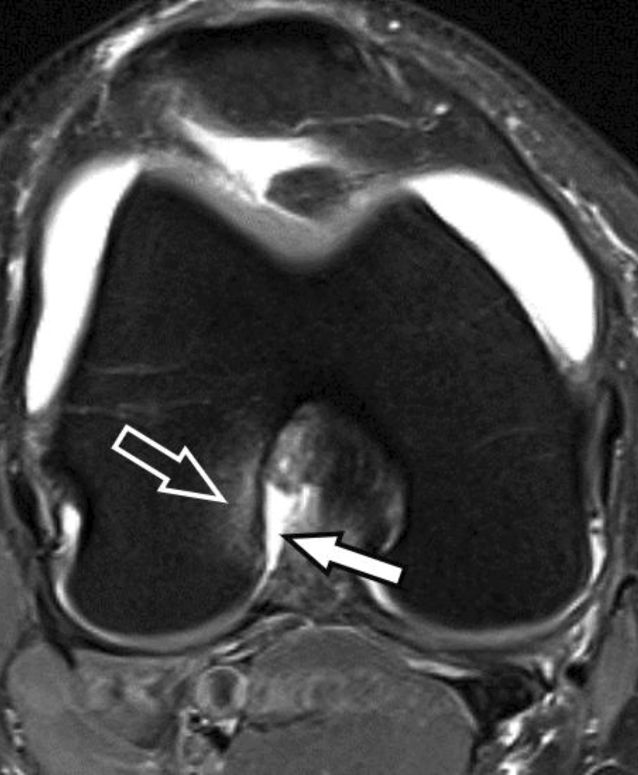

Abb. 5

MRT des Kniegelenks eines 38-jährigen Patienten nach Kniedistorsion. Die sagittale protonendichtegewichtete (PD) Sequenz mit Fettsuppression zeigt eine nichtdislozierte Avulsionsfraktur der Eminentia intercondylaris mit hyperintenser Frakturlinie (hohler Pfeil), verursacht durch Zug des vorderen Kreuzbands (VKB). Es besteht eine Signalerhöhung des VKB (weißer Pfeil) als Zeichen einer Zerrung bzw. von interstitiellen Mikrorupturen. Am weit anterioren tibialen Ansatz des VKB besteht zudem eine sehr kleine Partialruptur in Angrenzung an ein winziges Knochenfragment (Pfeilspitze)